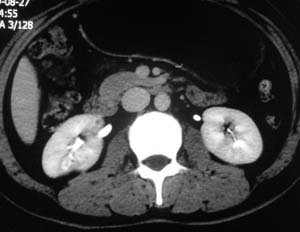

以下是引用子期在2010-3-19 20:47:00的发言:[br]血管畸形的ct增强应该有明显强化,本例并不相符合。本例双肾局部的略低密度影,累及肾盂,局部皮质明显变薄、内陷,增强扫描有轻度的强化,应考虑为炎性病变,患者为年轻男性,累及双肾的感染以结核较常见,可以没有明显的临床症状,尿中有时候也并不能查出什么;肾脓肿常有明显感染中毒症状,本例不符,另外一般的肾盂肾炎或肾小球肾炎通过小便就可确诊,其它还不能排除的是黄色肉芽肿性肾盂肾炎,然而单凭ct一般也很难鉴别。